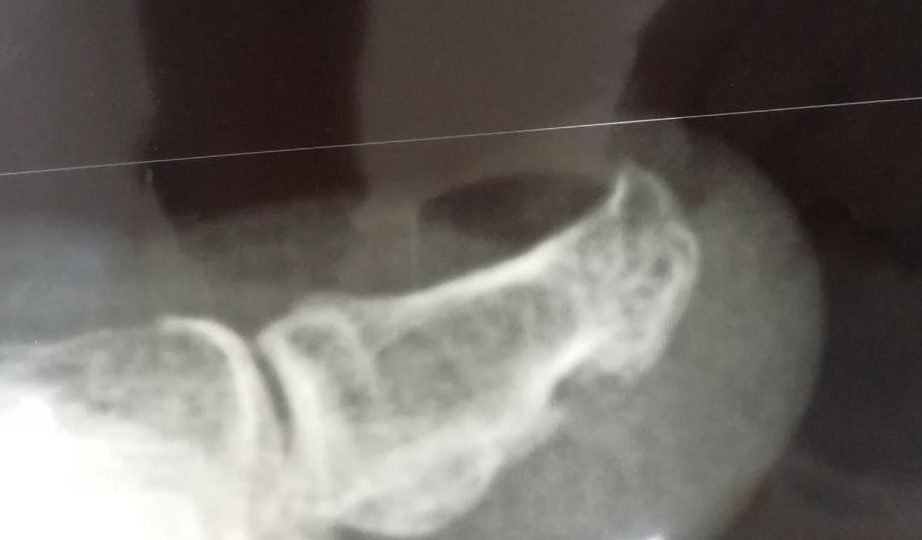

Ноготь медленно растёт, и палец болит

Каждый день к нам обращаются клиенты с гипертрофированным передним валиком и отсутствующей передней частью ногтевой пластины. Часто такие случаи определяют как экзостоз, просто глядя на увеличенный размер переднего валика пальца, особенно на первых пальцах стопы. Но что на самом деле представляет собой экзостоз и как с ним бороться? Экзостоз — это доброкачественное образование новой костной ткани на поверхности костей. Этот термин находит своё применение в различных медицинских контекстах и может быть известен под другими названиями, такими как остеохондрома, хондрома или остеофит. Каковы симптомы экзостоза? Экзостозы могут вызывать различные симптомы, включая: Внешние причины Внутренние причины Осмотр подолога при подозрении на подногтевой экзостоз включает сбор анамнеза, визуальную оценку деформации ногтевой пластины (поднятие, скручивание, онихолизис) и пальпацию, выявляющую твёрдый болезненный нарост. Специалист оценивает степень воспаления, состояние кожи, а для подтверждения диаг